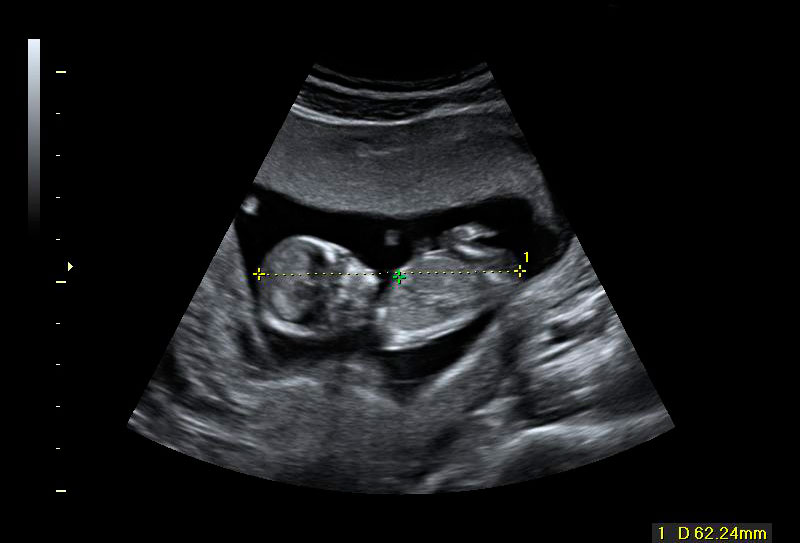

Ecografía Embarazo 2D y 3D Semana 12 - PLIEGUE NUCAL

Ecografía Embarazo 4D Semana 12 - PLIEGUE NUCAL